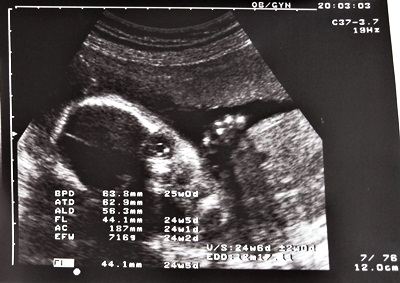

24w6d.JPG

(24w6d)有個水汪汪的大眼睛!